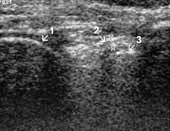

Рис. 2. I стадия остеоартроза. Умеренное увеличение b. suprapatellaris

(1+) с наличием избытка относительно однородной жидкости, 2 — надколенник,

3 — бедренная кость.